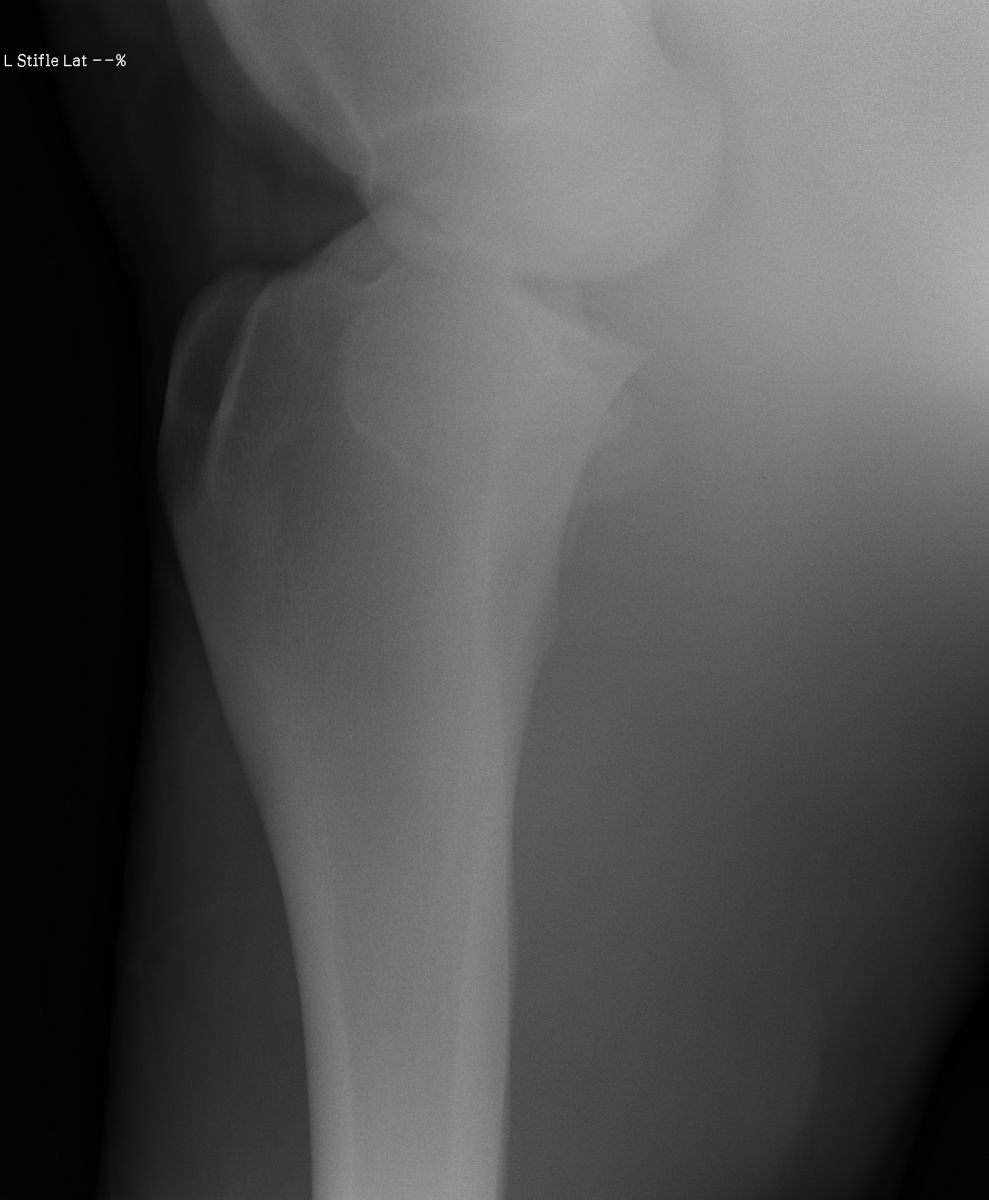

添付のレントゲン画像をご確認ください。現状渡しのノークレームノーリターンでお願いいたします。記載事項に関するキャンセルには応じられません。

※2022年12月17日の競走にて左後脛骨不全骨折を発症しています(全治6~9ヵ月)。